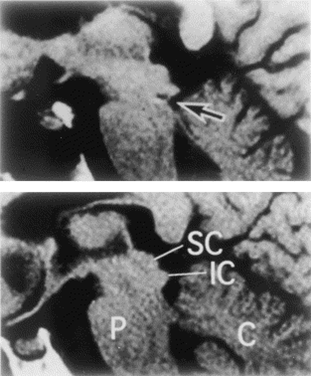

Figure 2 – Punctate hematoma of the inferior colliculi (bilateral),

caused by head trauma in a skiing accident, and thought to have

resulted from impact from the free edge of the cerebellar tentorium

(from Johkura et al. Defective auditory recognition after small

hemorrhage in the inferior colliculi. J Neurol Sci 1998;161:91–96).